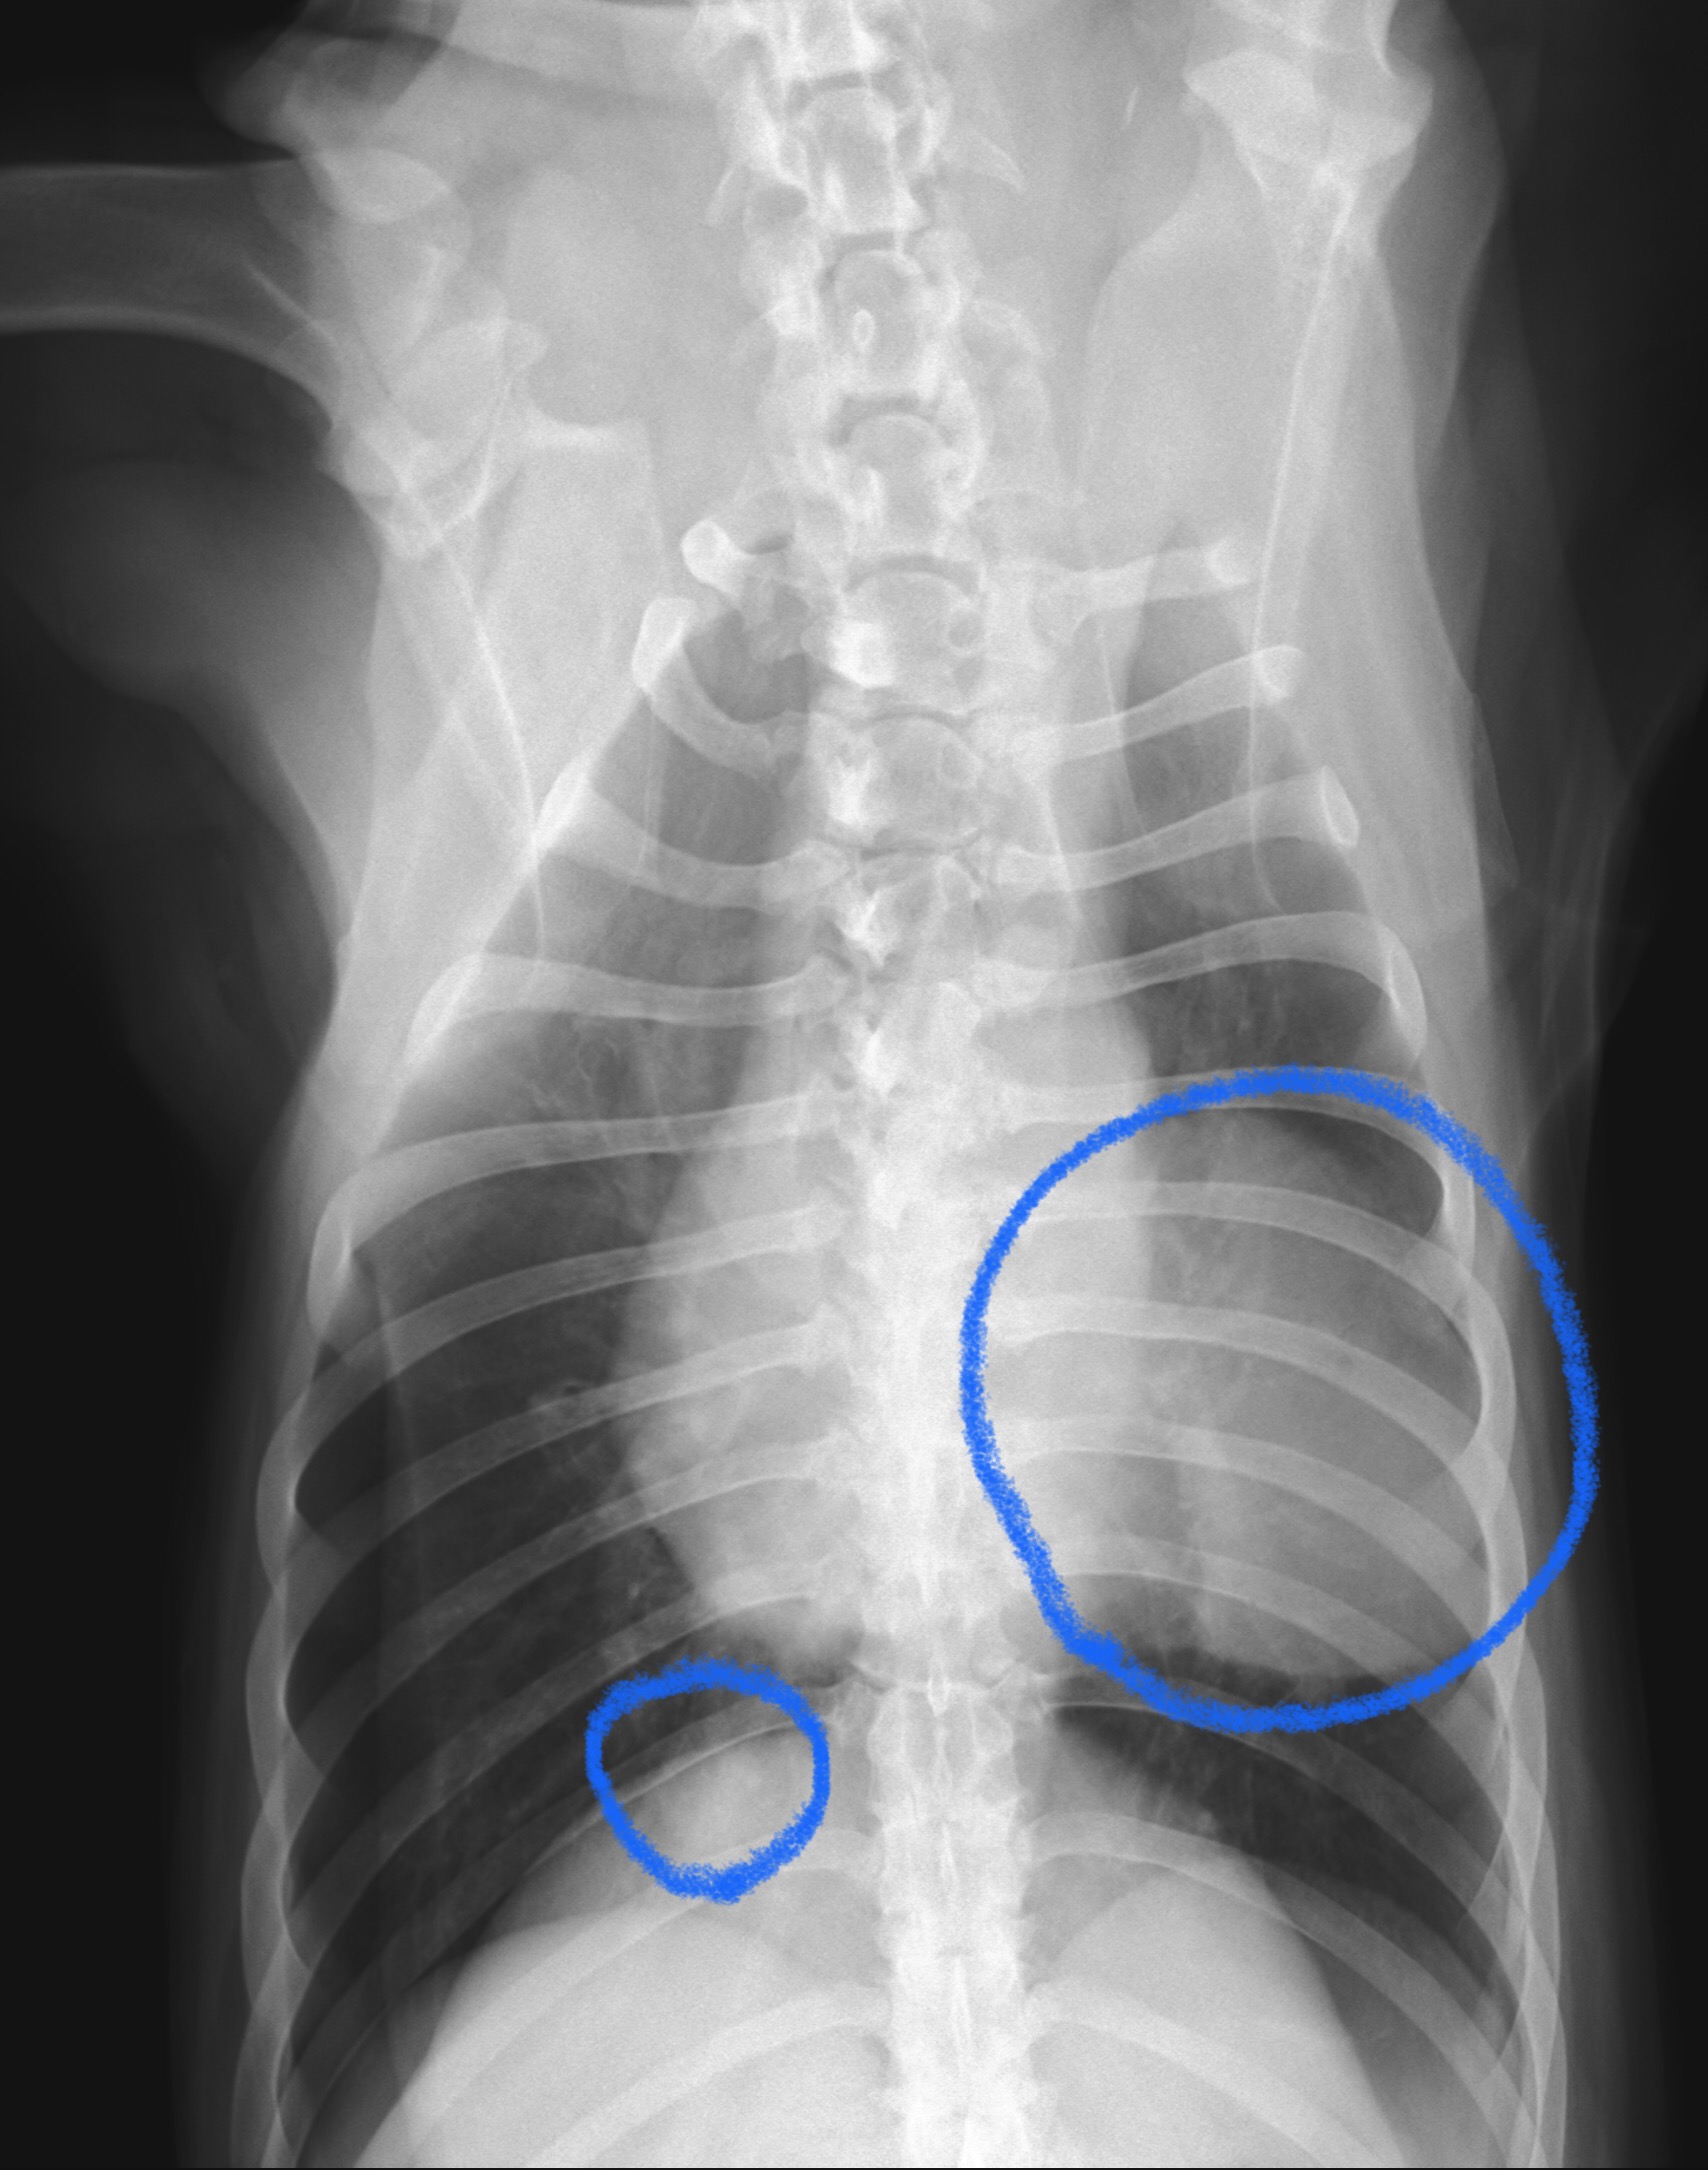

こんにちは。獣医師の永井です。今回は、肺腫瘍についてです。 ワンちゃんの肺腫瘍の発生は、人と比べて発生は稀であ…]]>

こんにちは。獣医師の永井です。今回は、肺腫瘍についてです。 ワンちゃんの肺腫瘍の発生は、人と比べて発生は稀であ…]]>